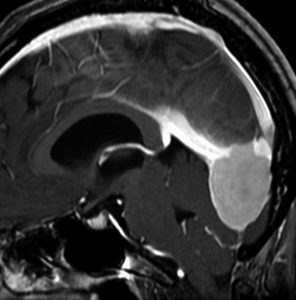

30代の女性に発生した髄膜腫です,一見すると松果体細胞腫と見分けはつきません。右の画像に見られるように典型的な中脳水道狭窄を生じていました。

軽度の閉塞性水頭症もありますが,頭痛も無く無症状なので経過を観察しました。髄膜腫だと診断できるのは,右の画像で見られるようにガレン大静脈が右側に偏っているからです。松果体細胞腫の場合は,ガレン大静脈は上方に変位します。

1年間経過観察したら水頭症が進行して脳室が拡大,腫瘍のサイズも大きくなりました。右側の画像で見られるようにガレン大静脈の左側のテントの下面から発生した髄膜腫でした。

左は手術直後の画像です,手術は左側のテント下面を見るために,後頭部経テント法 OTA occipital transtentorial approach で,小脳テントの左側を切断して腫瘍を全摘出しました。右側は6年後の画像ですが,腫瘍再発はありません。